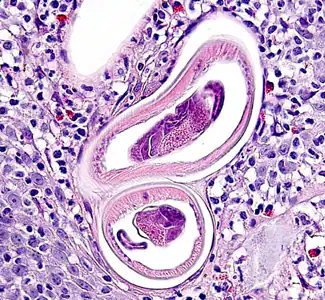

A 49-year-old man presented to his primary care physician with a lump in his throat which had developed over the past three months. He was ultimately referred to an oral surgeon with multiple oral ulcers and submucosal nodules. The patient was originally from Mexico, but has lived in Iowa for nearly 20 years, with recent visits back to Mexico in the past two years. The patient currently works as a landscaper, but has also worked in a foundry and on a pig farm. Biopsy specimens were taken from the submucosal nodules and sent to a pathology laboratory for routine histologic sectioning. Figures A–F show what was observed in sections of the nodule, stained with hematoxylin and eosin (H&E). Figure A was taken at 100x magnification. Figures B and C were taken at 400x magnification. Figures D–F were taken at 1000x magnification. What is your diagnosis? Based on what criteria?

Figure A